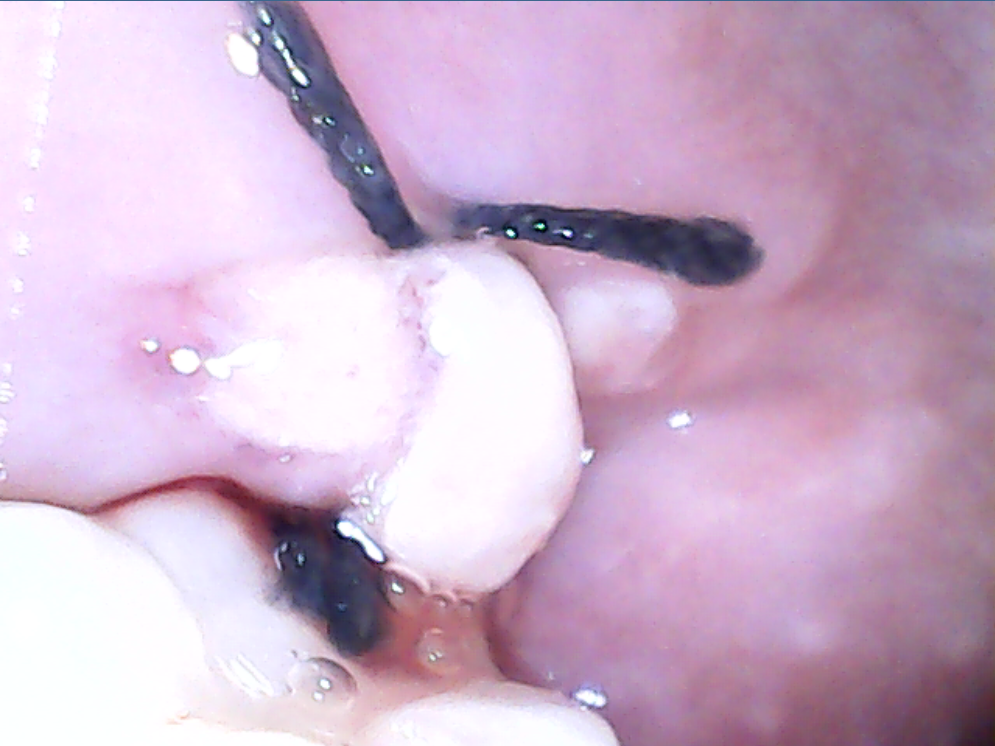

사랑니 발치 후 흰색으로 무언가가 있습니다

사랑니를 이번주 월요일 에 뽑고 지금 4일째 입니다. 이곳 흰색무언가가 나있는데 이게 어금니쪽으로 나있어서 뭐를 씹지도 못해요ㅠ 방금 사진찍는데 피고 나있네요...혹시 뭐 염증이나 그런거인가요? 제대로 아물고 있는건지... 대학병원에서 뽑아서 실밥 뽑기전(담주 수요일)까지는 병원가기도 힘들어서 걱정이 너무 크네요...

• 1번 째 사진